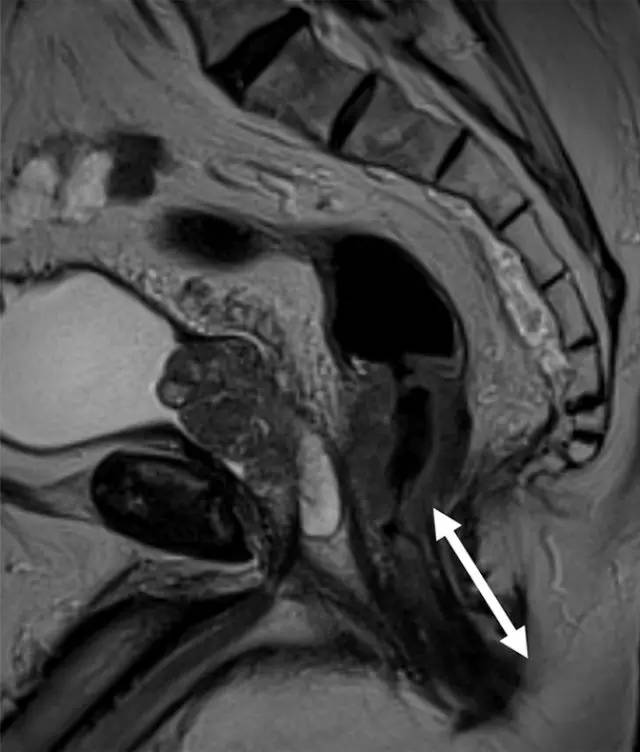

图 1 低位直肠癌患者的矢状 T2 加权图像。箭头显示肿瘤下缘距离肛缘 <5 cm。测量必须以相对直线的方式进行,以便与乙状结肠镜检查相符。